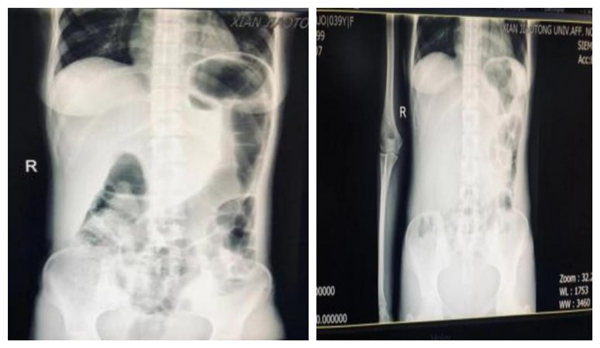

入院 X 线平片提示肠道积气,后证实为上消化道出血所致 抗酸、止血等处理后,积气减少